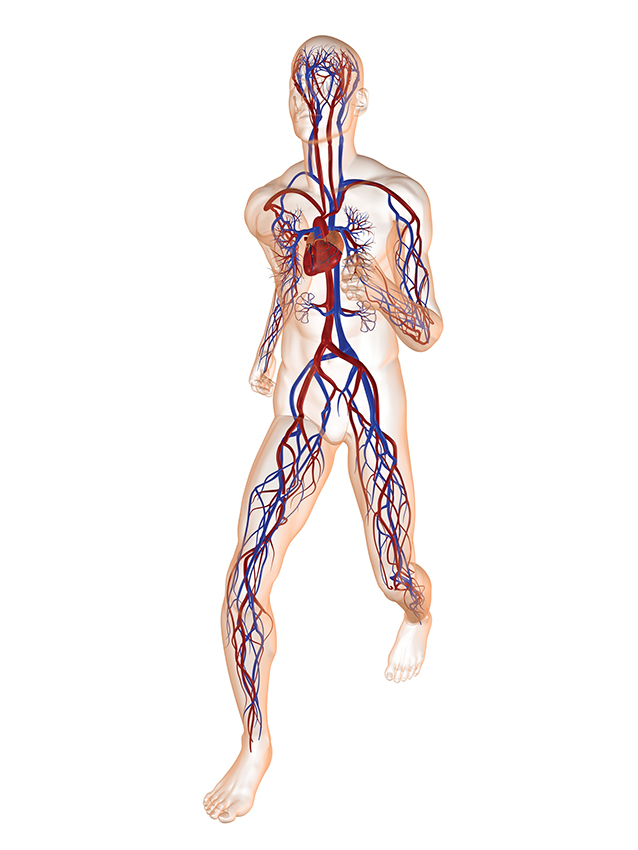

血液通過一個由動脈、靜脈和毛細血管構成的複雜系統之間循環。良好的血液循環是身體健康的前提。而該過程的核心環節便是氧氣和營養物質在血液和組織之間的交換,於此同時二氧化碳和廢物經過組織和血液後從而排出體外。

而這個交換過程正是通過分佈在身體各個部位的那些數不勝數的毛細血管壁進行的。

健康的血液流動

您的毛細血管是血液循環系統中最小的組成部分——保持毛細血管健康大有裨益。